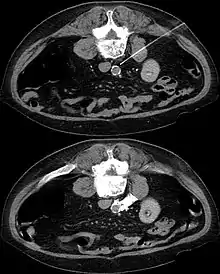

The sympathetic plexus can also be blocked in other parts of the body. Lying on the major abdominal vessels sympathetic plexus may, for example, under local anesthesia guided by a CT scan it can be turned off by injection of concentrated alcohol (interventional radiology).

In CT guided lumbar sympathicolysis, the site of neurolytic solution injection is chosen at the level of L2-L3 vertebra level. The needle should avoid the vertebral transverse process, ureter, pelvicalyceal system, and other major blood vessels. The target injection site would be anteromedial to the psoas muscle and dorsolateral to the abdominal aorta, where the sympathetic trunk would most likely be located.[1]

After the skin of the puncture site is cleaned, 2% lignocaine is injected into the to numb the skin and also the needle trajectory. Then a 22G China needle is inserted into the target site, which is bounded by the vertebral body, aorta, inferior vena cava, and psoas muscle. This region houses the lumbar sympathetic ganglion. Then, iodinated contrast medium (iohexol) and lignociane is injected into the target site to check the position of the needle tip. Once the needle tip position is confirmed, a mixture of neurolytic solution (99.9% alcohol) and iodinated contrast medium (at a ratio of 10:1) is injected into the target site.[1]